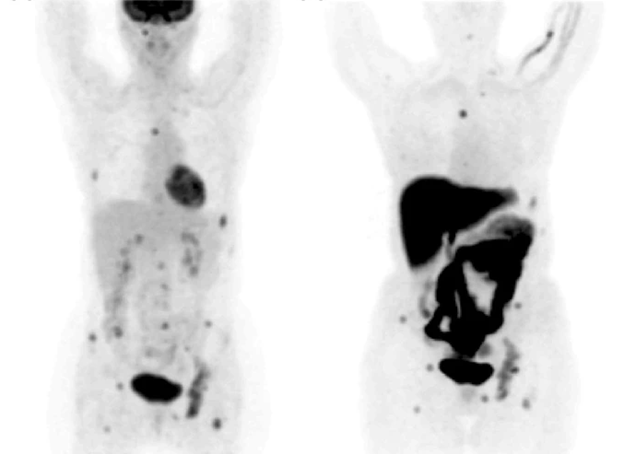

Positron Emission Tomography (PET) is an imaging technique that takes advantage of the high glucose consumption of malignant cells by measuring the uptake of 18F-FDG, a glucose derivative (25). 18F-FDG is transported into tumor cells through the cell membranes by glucose transporters Glut-1 and Glut-3, and it is then phosphorylated by hexokinase. Factors such as inflammation and reduced oxygen levels also increase the retention of 18F-FDG in tumor cells (25). PET has high specificity in detecting breast cancer, ranging between 71% and 95% and high sensitivity, ranging between 80% and 90% (25). PET was found to be twice as sensitive as mammography and ultrasound combined in terms of detecting breast cancer (25). However, its sensitivity decreases significantly when detecting some tumors, due to their small size, metabolic activity, subtype, growth pattern, and proliferation rate (26). On the contrary, the sensitivity and specificity of PET are not affected by tumor cell percentage, lymph node status, histopathological grade, steroid receptor status, the presence of inflammatory cells, or GLUT-1 receptor expression (26). When comparing the efficiency of PET with MRI in detecting primary tumors, no significant difference was found. However, PET is highly accurate in detecting axillary nodal metastasis, with sensitivity ranging between 79% and 100% and specificity ranging between 66% and 100%. PET sensitivity in detecting ductal carcinoma was about 66% whereas its sensitivity in detecting lobular carcinoma was about 25% (27). This difference in sensitivity resulted in arguing that PET is insufficient to diagnose breast cancer, in addition to its high cost. However, it was shown that PET was significantly accurate in detecting local recurrent breast cancer and distant metastasis (Figure 1), accounting for 89% to 98% accuracy. Additionally, PET is more accurate than mammography and CT in detecting mediastinal and internal mammary nodes involvement (25).

Figure 1: PET showing recurrent breast cancer metastasis in the bone (25).